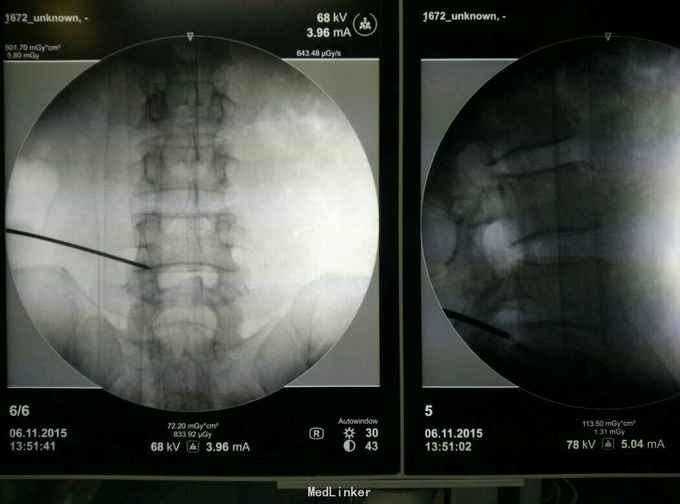

患者,男,42岁,因“左下肢疼 痛麻木一个月”入院。一个月前有搬重物的病史。

查体:L45间隙压痛,左侧小腿外侧及左足拇趾感觉减退,左下肢肌力四级,左侧下肢直腿抬高试验30度阳性。腰椎MR提示: L4/5椎间盘脱出向上高度游离,压迫左侧神经根。

诊断:L45腰椎间盘脱出游离。 治疗:行侧路椎间孔镜手术。